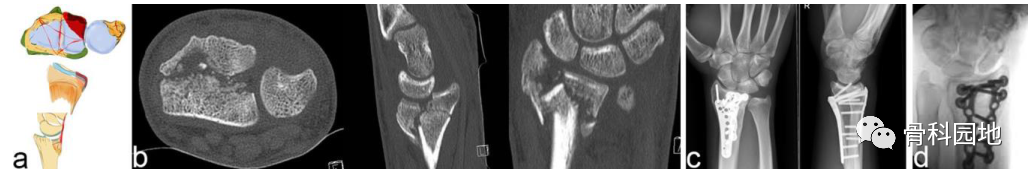

2、掌侧关节骨块

注:可以是大的或较小的边缘碎片。可能发生掌侧脱位,而背侧韧带保持完整 (a)。掌侧骨块:重要的尺桡韧带和尺腕韧带的起源 (b)。向掌侧脱位(c)。掌侧骨折从尺侧延伸到桡侧(d)。在 X 光平片上很容易忽略小的掌侧尺骨骨块,但轴位 CT 扫描容易显示该骨块 (e)